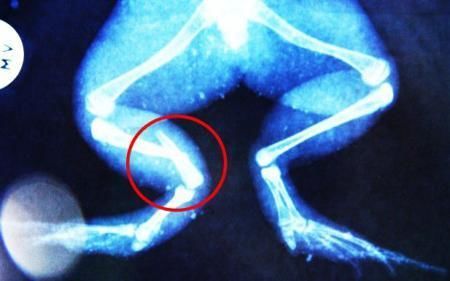

環(huán)球網(wǎng)4月2日?qǐng)?bào)道 據(jù)《每日郵報(bào)》報(bào)道,上個(gè)月,南非大牛蛙布魯萊的右小腿被鄰居家的一只狗咬到,導(dǎo)致粉碎性骨折,現(xiàn)在經(jīng)過(guò)2個(gè)小時(shí)的手術(shù),它的斷腿已經(jīng)被接上,它也因此成為有史以來(lái)第一只通過(guò)外科手術(shù)用鋼針接上斷腿的青蛙。

野生生物專家安妮經(jīng)常為學(xué)校寫教材,她認(rèn)為這是人類第一次通過(guò)手術(shù)給一只青蛙接斷腿。在手術(shù)開(kāi)始階段,獸醫(yī)把少量給狗用的麻醉藥注入到這只青蛙體內(nèi),讓它失去知覺(jué)。然后他在布魯萊的斷腿上切開(kāi)一個(gè)小口,把一根小鋼針植入腿里。最后獸醫(yī)給它縫了9針,把切口縫合在一起。僅僅幾周后,布魯萊就能在安妮家附近活動(dòng)了。這只青蛙大約已有25歲,主要以嚙齒動(dòng)物、蛇和其他青蛙為食。布魯萊所屬的牛蛙種群正在不斷減小,目前只能在非洲南部的濕地里才能看到這種青蛙。